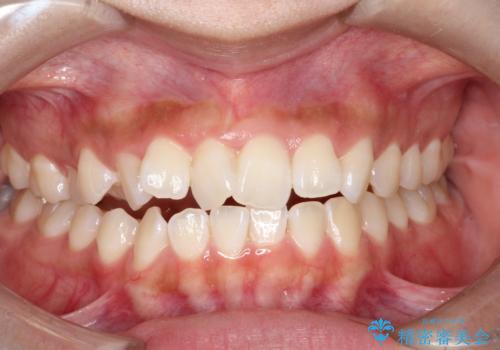

【インビザラインで再矯正】マウスピース矯正で隙間を閉じたい

- 過去に矯正を行ったあと、前歯の後戻りを主訴に来院されました。

マウスピース矯正にて隙間を閉じる計画をたて、治療を行いました。